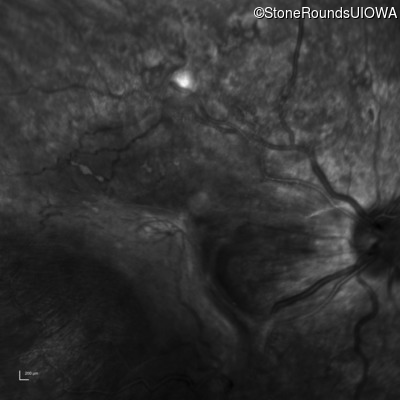

Fluorescein Angiography - Right - Count Fingers 3'

Exemplar

Fluorescein Angiography - Left - 20/400 sc